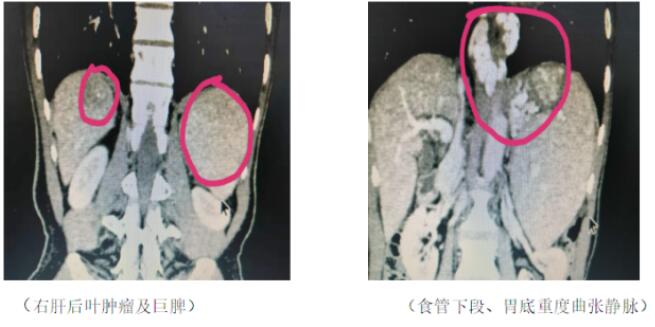

患者為一名53歲男性,因“牙齦出血1月”入院,既往半年前因“上消化道大出血”行“食管下段曲張靜脈套扎術(shù)”。完善相關(guān)檢查后診斷為:1、乙肝,丙肝,肝炎后肝硬化,右肝后葉(VII段)腫瘤;2、門靜脈高壓癥,脾亢,巨脾,白細(xì)胞減少,血小板減少,食管下段、胃底靜脈重度曲張。該名患者肝腫瘤位于右肝后葉(VII段),位置較深且隱蔽,非常不好暴露;門靜脈高壓癥病人,腹腔內(nèi)曲張血管叢非常多,靜脈壁薄易出血,稍有不慎,就會腹腔大出血危及病人生命。經(jīng)過科室討論,認(rèn)為該手術(shù)非常復(fù)雜、難度大、風(fēng)險高,極具挑戰(zhàn)性。

2020年1月9日,在麻醉科及手術(shù)室護(hù)士團(tuán)隊的配合下,手術(shù)團(tuán)隊精心操作,克服艱難險阻,歷時8小時,在3D腹腔鏡下先切除巨大脾臟、然后離斷賁門周圍曲張血管,最后游離右肝,切除肝VII段腫瘤。手術(shù)過程順利,出血約100ml,未輸血。